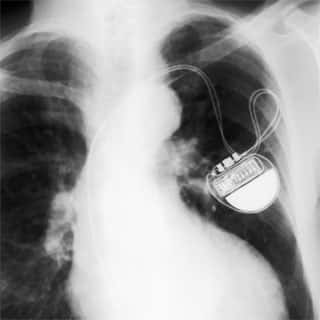

Marcapasso cardiológico

Devemos o desenvolvimento desse equipamento, muito utilizado nos dias de hoje, aos trabalhos de um famoso cardiologista, Paulo Maurice Zoll, que durante grande parte de sua carreira, dedicou-se ao estudo dos estímulos elétricos no coração, com a finalidade de evitar paradas cardíacas.

Zoll estimulava eletricamente o coração através de eletrodos externos, colocados no peito do paciente. Hyman concluiu que se os estímulos fossem feitos diretamente no coração, os resultados seriam melhores.

Somente após a II Guerra Mundial, por volta de 1950, foi desenvolvido um marcapasso totalmente eletrônico, mas volumoso. Somente após o desenvolvimento dos transistores é que os marcapassos foram realmente miniaturizados, chegando a volumes compatíveis com sua inserção no coração.